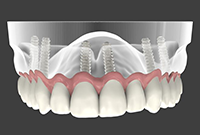

Impianti dentali

Implantologia immediataQuante visite dovrò fare per un restauro completo della bocca?